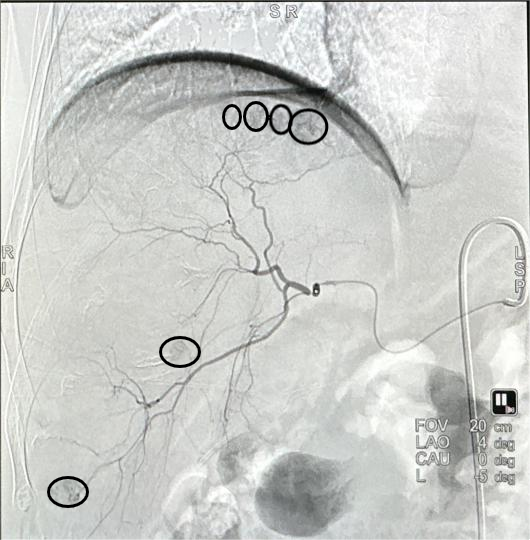

一切准备就绪,放射科主任罗谞成协助朱晖教授进行介入手术。穿刺点局麻后,朱晖教授在B超引导下穿刺插管,在DSA设备的帮助下,对肝右及肝中动脉较纤细、远段分支位置的六处结节进行精准打击。术中,朱晖教授把导管送进肝肿瘤的供血动脉中对其进行栓塞,阻断其血供,使肿瘤趋于坏死,并向病灶集中释放药物。手术非常顺利,历时仅2小时。由于患者血小板较低,为防止血肿的发生,朱晖教授亲自按压止血30分钟,确定穿刺处无出血、无血肿后,再进行加压包扎。最后安全护送患者至病房,并进行了详细的术后指导。患者及家属不胜感激:“这趟求医之路实在值得,朱教授又救了我一命,谢谢你们!”短短三次“相遇”,用心用情的“守护”,铸就一段医患深情。

术前造影